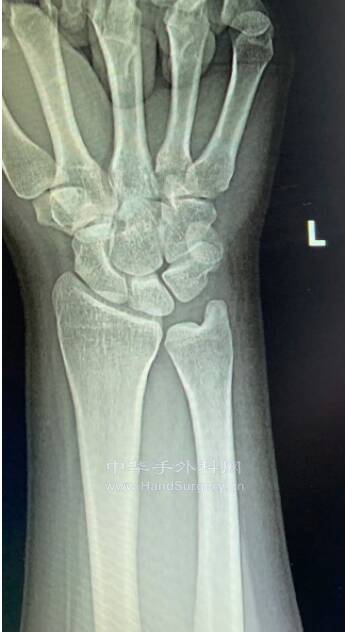

mmexport1652862362313.jpg

mmexport1652862365265.jpg

mmexport1652862371301.jpg